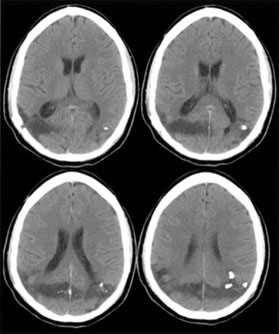

Cerebral blindness is distinguished from ocular disease by both normal pupillary light responses and normal fundoscopic examination. These may lead to an erroneous diagnosis of factitious visual loss. Associated signs of damage to parietal or temporal structures help to confirm cerebral blindness but may not always be present. Visual evoked potentials are of limited diagnostic value. They can be altered voluntarily by subjects without visual loss67 and can be normal in patients with striate lesions.68,69 They cannot differentiate between blind and seeing children with neurologic disease,70 and normal or abnormal results do not predict visual outcome.60,71 Absent evoked responses are rare and may only occur early in the course.70 Absent alpha rhythm on electroencephalography72,73 is reportedly a more sensitive diagnostic sign than abnormal visual evoked potentials.60 CT scans can be normal, but modern MR imaging with coronal images through the occipital lobe should reveal most striate or optic radiation lesions with complete and persistent visual loss (Fig. 16). Single photon emission computed tomography (SPECT) scans may reveal bilateral functional defects in cases with unilateral MRI lesions.74

Fig. 16. CT scan of man with cerebral blindness after a gunshot wound.